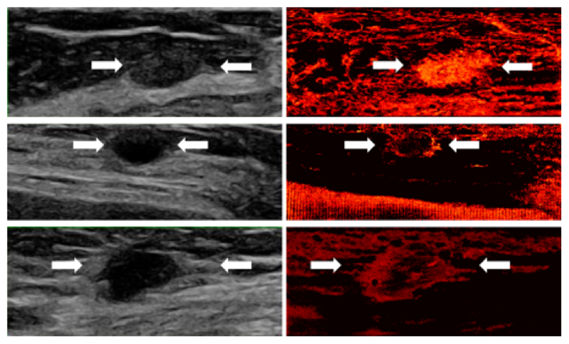

Super-resolution demonstrations in human ultrasound scans show the vascular characteristics of three types of breast lesions:

Top (Fibroadenoma - benign): The super-resolved image reveals an oval, well-circumscribed mass with uniform, dense vascularization.

Middle (Cyst - benign): The recovery highlights peripheral vascular concentration surrounding a round, avascular core.

Bottom (Invasive Ductal Carcinoma - malignant): An irregular, ill-defined mass with sparse central and dense peripheral vasculature.

Super-resolution vascular imaging of three breast lesions: fibroadenoma (top), cyst (middle), and invasive ductal carcinoma (bottom).